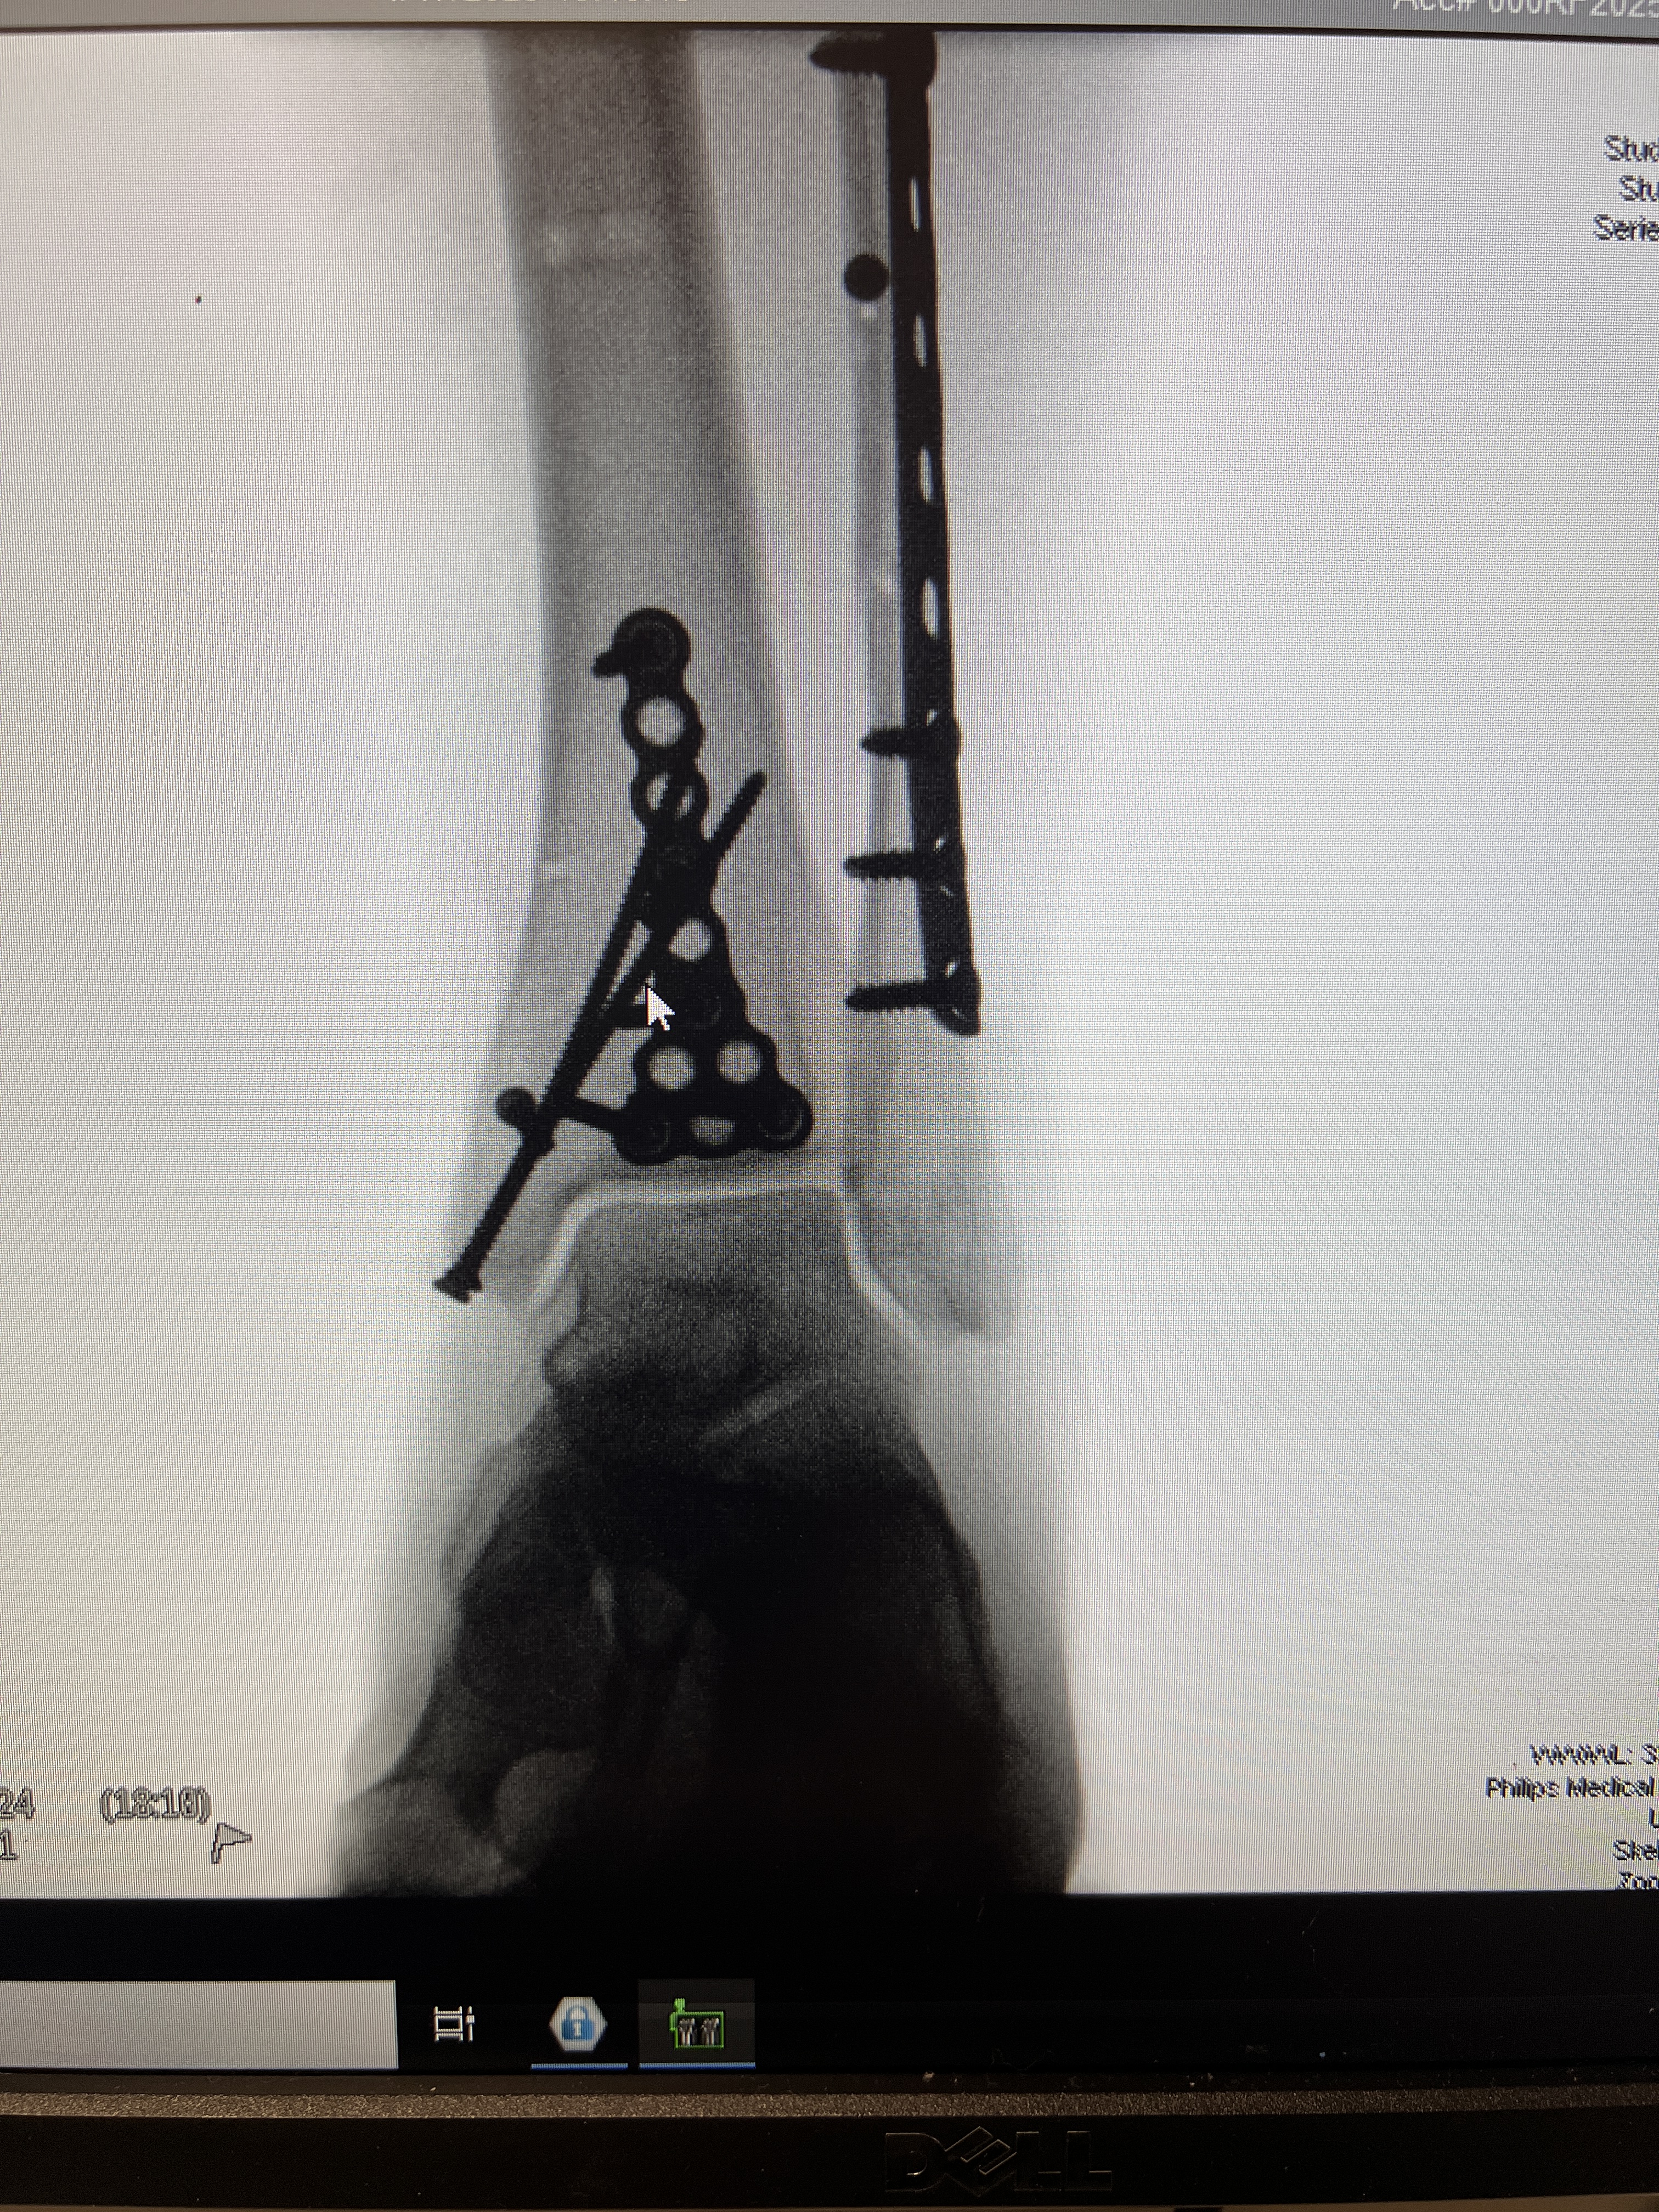

Sometime after daybreak, the orthopedic trauma surgeon Dr. Wharton visited me where I was waiting in the ER lobby area. He explained that I would be having two surgeries. The first would be that morning. This surgery would stabilize my ankle. He would be installing an external fixator , metal pins or wires that are inserted into the bone through the skin and connected to an external frame, creating a “cage” appearance. Dr. Wharton prepared me for awakening from surgery to see this metal cage around the lower half of my left leg and ankle. I was simply thankful that my ankle would be surgically repaired; however, I was also mental fixated on whether I would be able to go on our big family Europe trip in June. That thought had come to me within minutes of breaking my ankle.

On Thursday afternoon April 17, 2025, I had my second and final successful ankle surgery at UNM Hospital. Dr. Wharton and his team installed all the internal hardware to support the healing of my three fractured bones. I did indeed feel like the Bionic Woman after I saw the x-rays days later. My husband managed through some hours of worry as my procedure started late and the orthopedic team did not update him promptly when I was out of surgery. He was grateful to join me when they wheeled me to my hospital room. We were both thankful to learn that the surgery went really well.